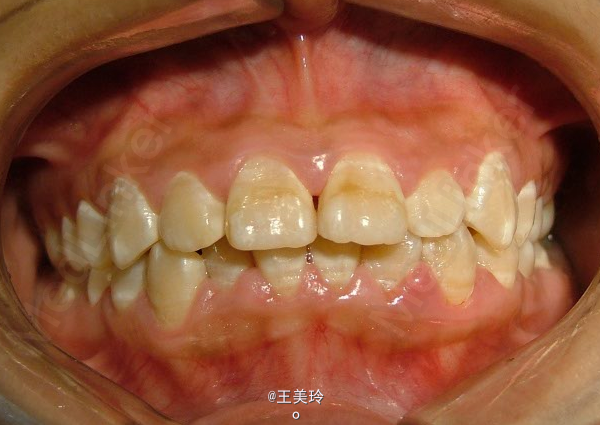

主诉:面突求矫治 既往史:无矫治史,无牙科治疗史,无外伤史,无过敏史,无口腔不良习惯,无家族遗传史 口腔检查:恒牙列,A7-B7;C7-D7。个别牙齿不齐 尖牙磨牙I类关系轻度深覆合深覆盖 下颌中线右偏约2mm 双颌前突,突面型 关节无弹响无压痛

诊断:安氏I类双颌前突 矫治计划 1.MBT矫治技术 2.拔牙矫治,拔A4B4C4D4 3.闭隙曲,J勾内收前牙 4.矫治结束后尖牙,磨牙,覆合覆盖正常 5.面型有所改善